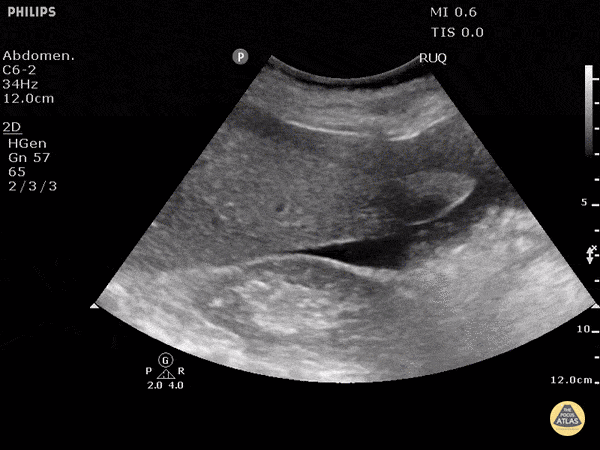

One Minute Image Review

One-Minute Image Review: High yield bite sized learning! Voice annotation of both normal and abnormal point of care ultrasound clips!